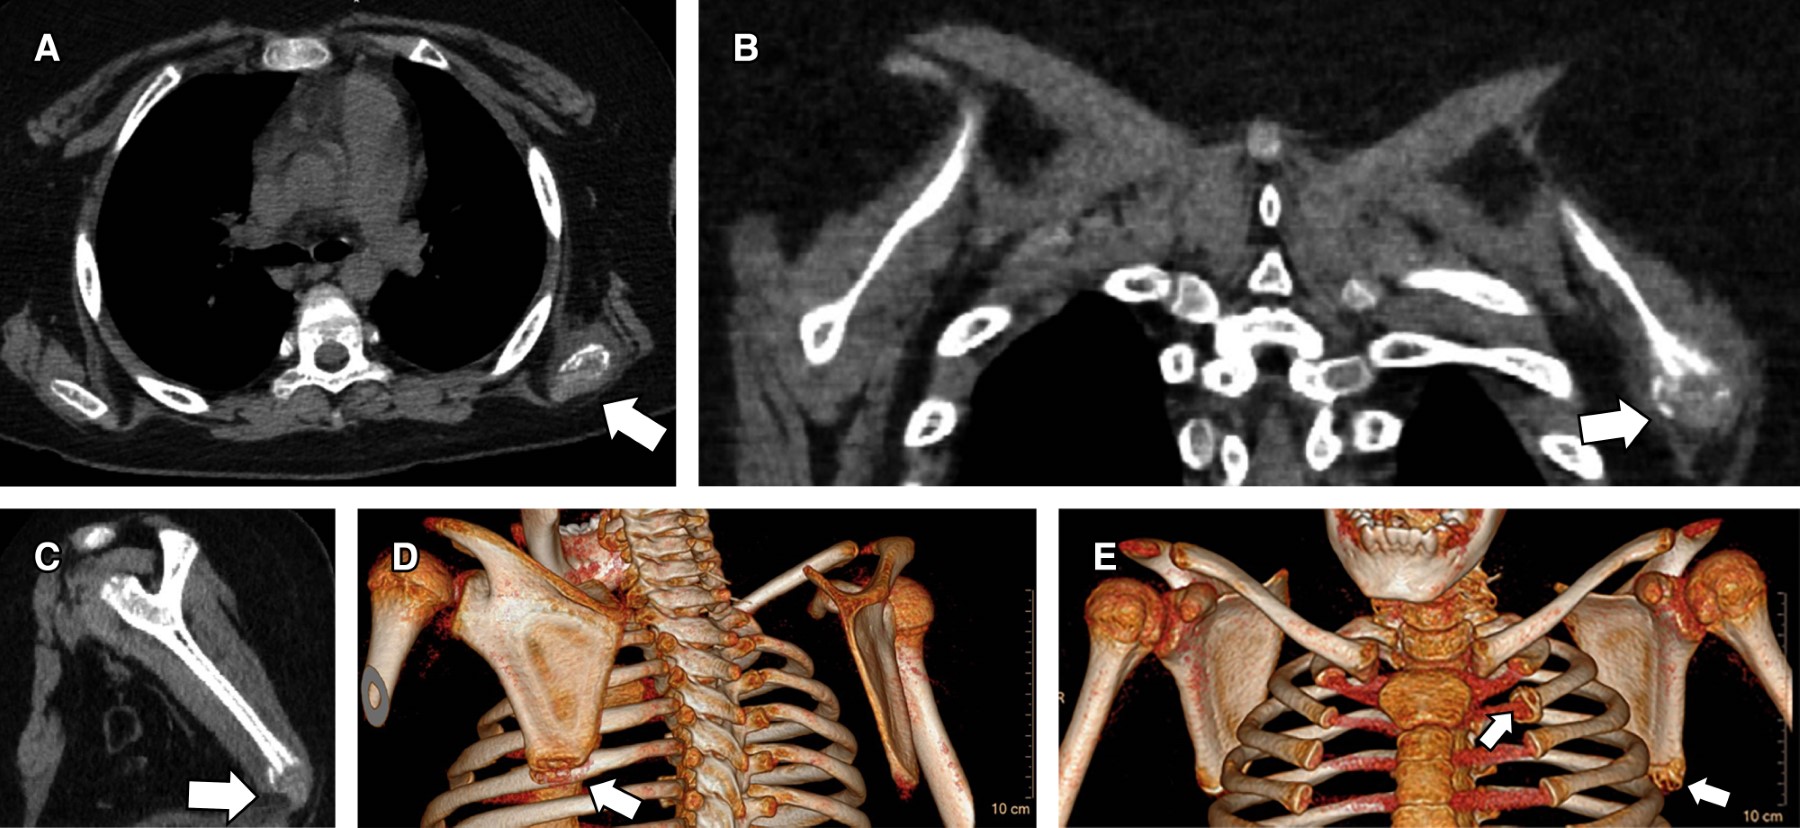

Reingresó a los siete días por neutropenia febril de alto riesgo, asociando nuevas lesiones similares a las descritas anteriormente. Se indicó PTZ, ciprofloxacina y TMS endovenoso. Por el mecanismo fisiopatológico de Aeromonas hydrophila se sospechó foco profundo productor de toxina que generaba lesiones secundarias en PPB. Se realizó gammagrafía ósea que mostró imágenes captantes en extremo anterior de la segunda costilla izquierda y ángulo escapular inferior izquierdo (Figura 2). Se completó con tomografía computada, la cual reportó lesiones líticas de bordes poco definidos y leve abombamiento de los planos blandos adyacentes, compatible con osteomielitis subaguda-crónica (Figura 3). Se realizó toilette y biopsia quirúrgica compatible con osteomielitis crónica, con cultivos negativos. Siete meses después se encuentra cumpliendo antibioterapia prolongada, sin nueva infección por dicha bacteria.

Osteomielitis. La osteomielitis por A. hydrophila raramente se ha reportado como sitio de infección extraintestinal.3-5 Ante la sospecha clínica, es indispensable la realización de radiografías y, cuando son negativas, está indicada la gammagrafía ósea.4